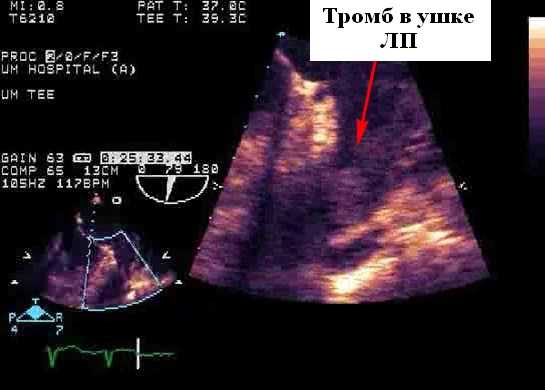

Литература, документирующая взаимосвязь между потенциальными источниками сердечно-сосудистой эмболии, ограничена тем фактом, что большая часть текущих данных основана на нерандомизированных сериях случай-контроль, а не на проспективных исследованиях. Потенциальные источники эмболов в сердечно-сосудистой системе лучше всего разделить на две группы в зависимости от уровня имеющихся в настоящее время доказательств: вероятные или возможные источники (таблица 1). Большинство из них происходит из-за эмболии внутрисердечного тромба, который в более чем половине всех случаев локализуется в пределах левого предсердия (ЛП), прежде всего в пределах ушка левого предсердия (УЛП). Фибрилляция предсердий и ревматическая болезнь митрального клапана (в первую очередь митральный стеноз) являются наиболее частыми предрасполагающими факторами. Тромб левого желудочка (ЛЖ), обычно возникающий в условиях серьезной аномалии движения апикальной стенки (акинезия или аневризма), является вторым наиболее частым потенциальным источником эмболии (25%). Большие вегетации и левосторонние опухоли (миксома или папиллярная фиброэластома) встречаются гораздо реже. Все чаще на эхокардиографии выявляется атерома грудного отдела аорты, которая связывается с эмболическими событиями. Эта связь наиболее высока для «сложных» бляшек (например, толщиной> 4 мм или поражений на ножке и подвижных тромботических наложений). Острое ишемическое событие у пациента с протезом механического клапана является кардиоэмболическим, пока не будет доказано обратное.

Оценка межпредсердной перегородки и грудной аорты. В целом чреспищеводная эхокардиография (ЧПЭХоКГ) выявляет значительно больше потенциальных источников эмболии, чем TТЭхоКГ (39-57% против 15-19%). Оценка потенциального источника эмбола в настоящее время является основным клиническим показанием для ЧПЭХоКГ в большинстве лечебных учреждений (26%). Использование контраста могло бы повысить эффективность ЧПЭхоКГ для обнаружения тромбов в ушке левого предсердия, и польза была максимальной, когда исследования были ограничены наличием спонтанного эхо-контрастирования или когда была низкая скорость опорожнения ушка левого предсердия. Кроме того, контраст часто помогает отличить плотный спонтанный эхоконтрастный осадок и необходим для оптимальной визуализации ЛП и тромба, в частности, расположенной сзади ушка левого предсердия (наиболее частое место расположения тромба). Однако, вероятно, лучше рассматривать эти два метода как взаимодополняющие, а не исключающие друг друга.

- Тромбоз ушка левого предсердия